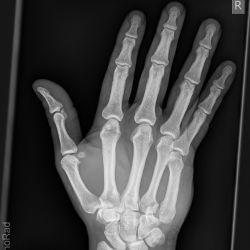

Reversed Bennett-Fraktur